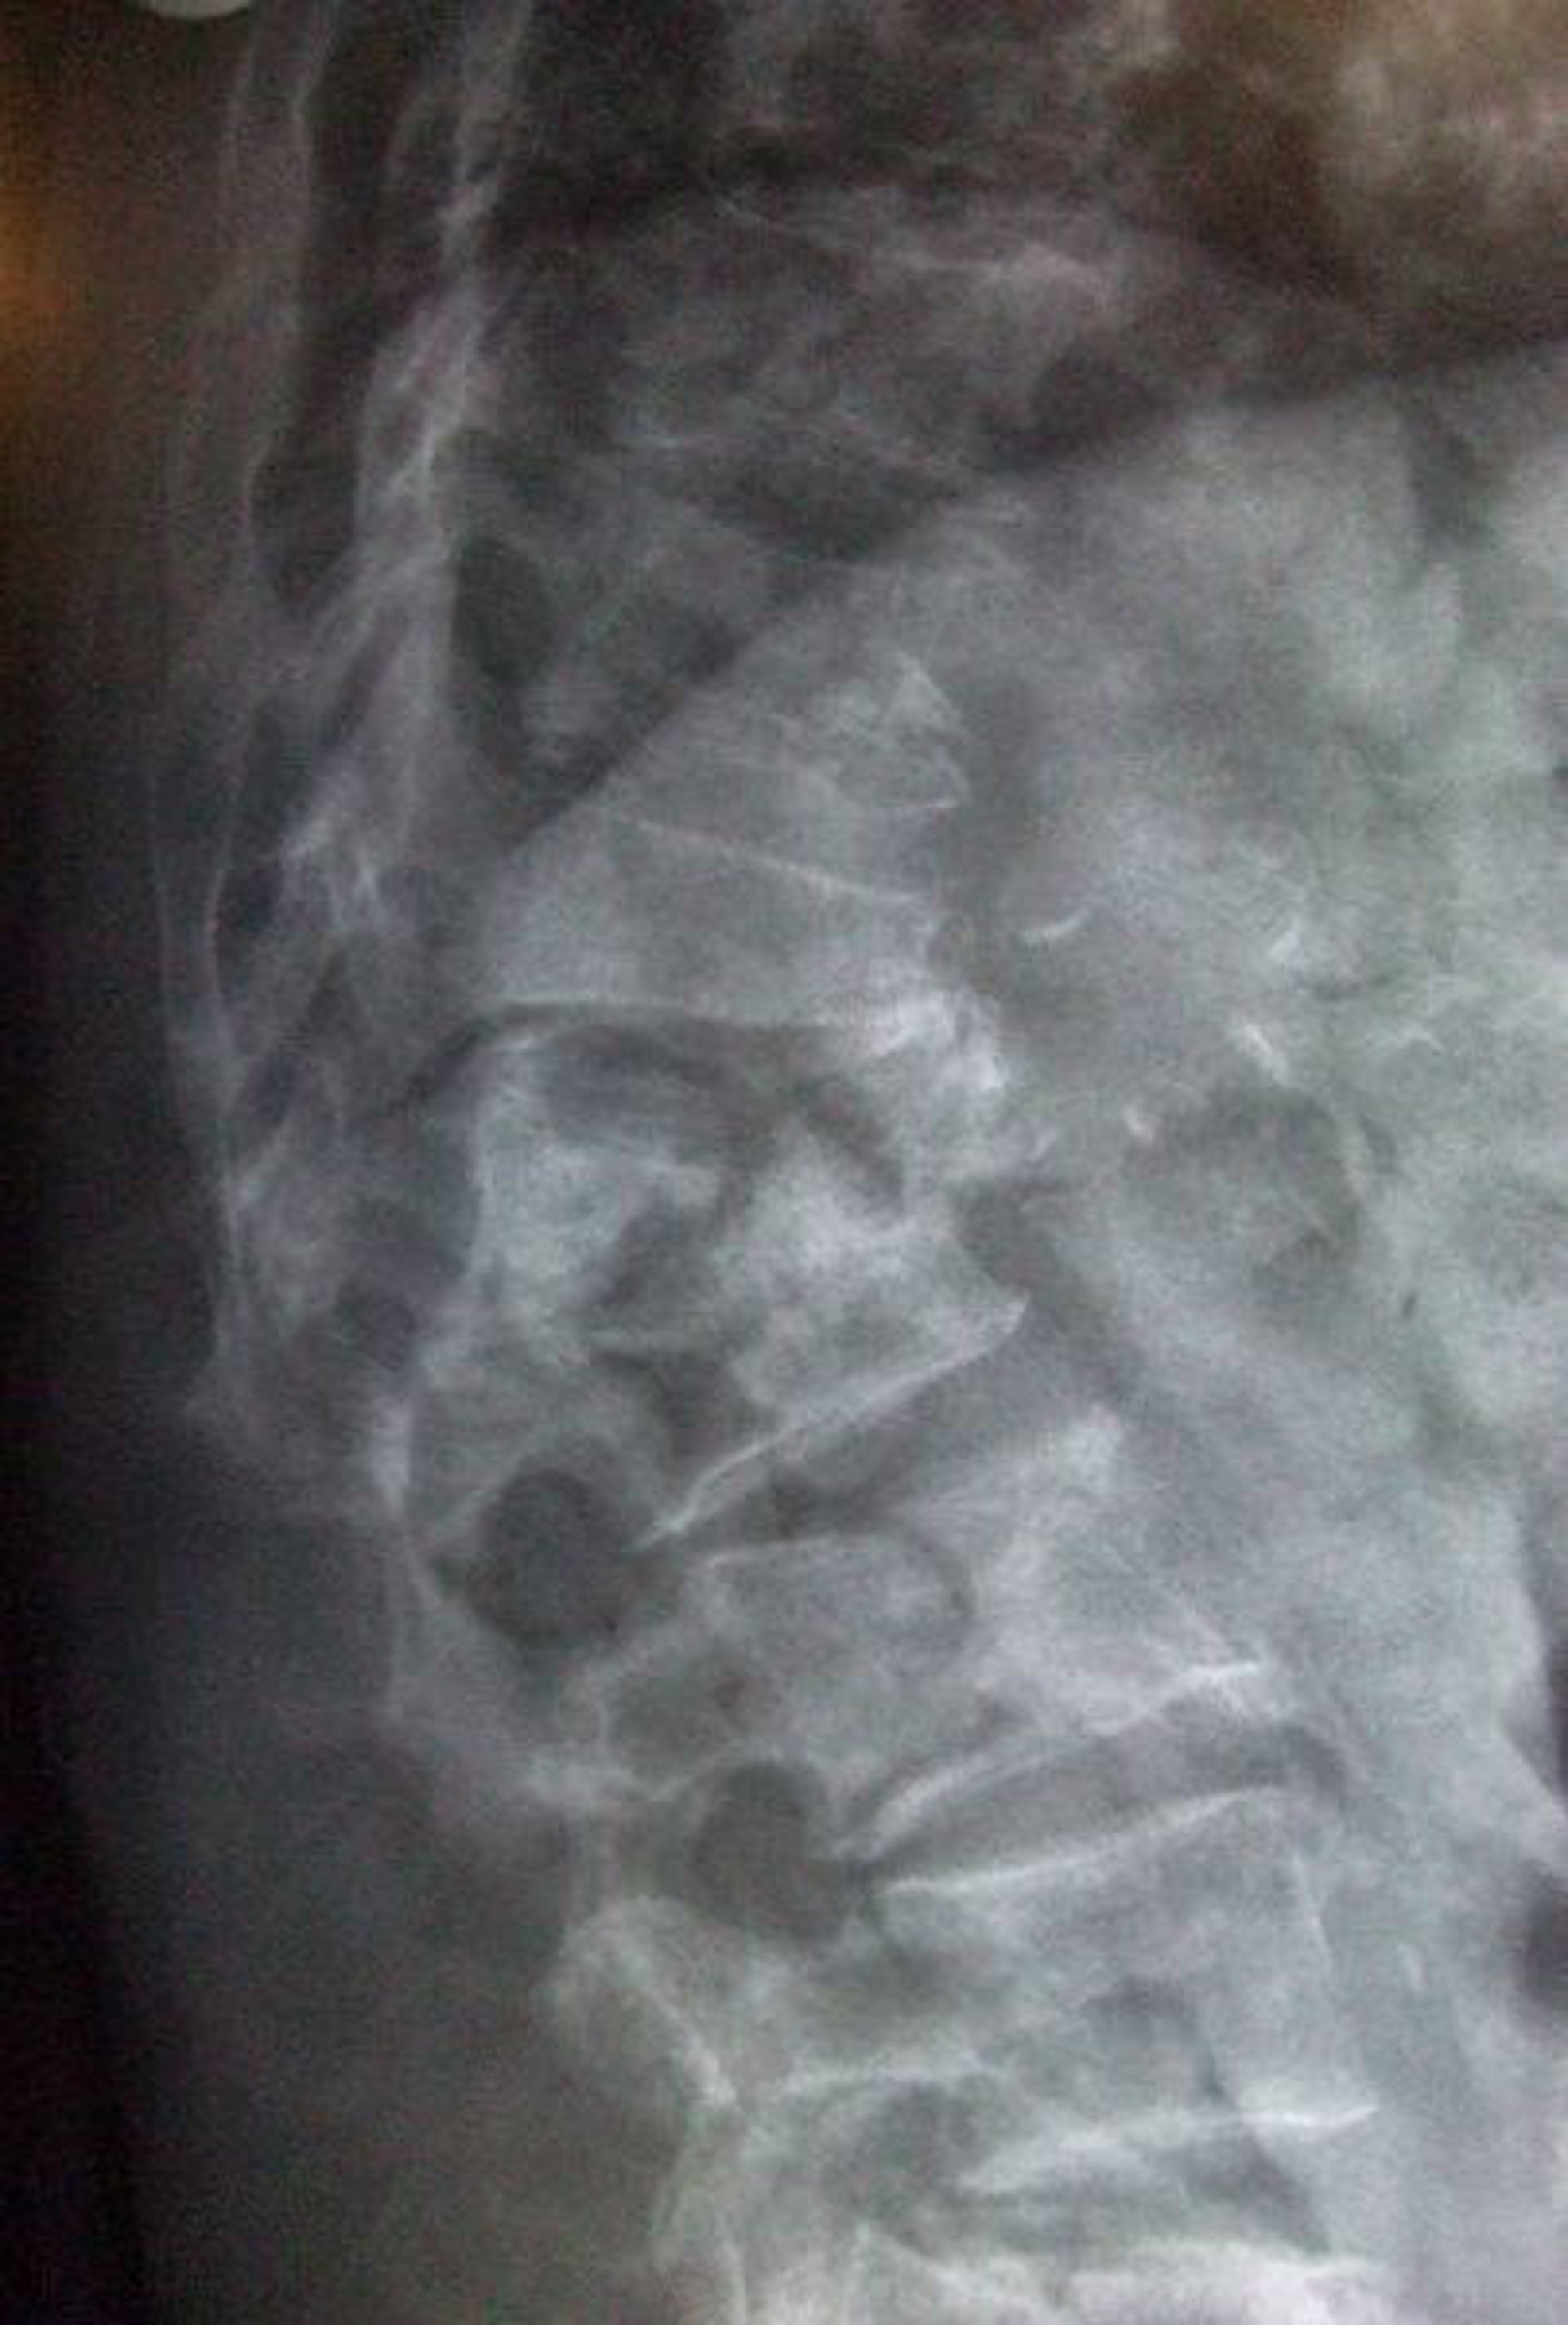

osteoporosis

WIKIMEDIA COMMONS